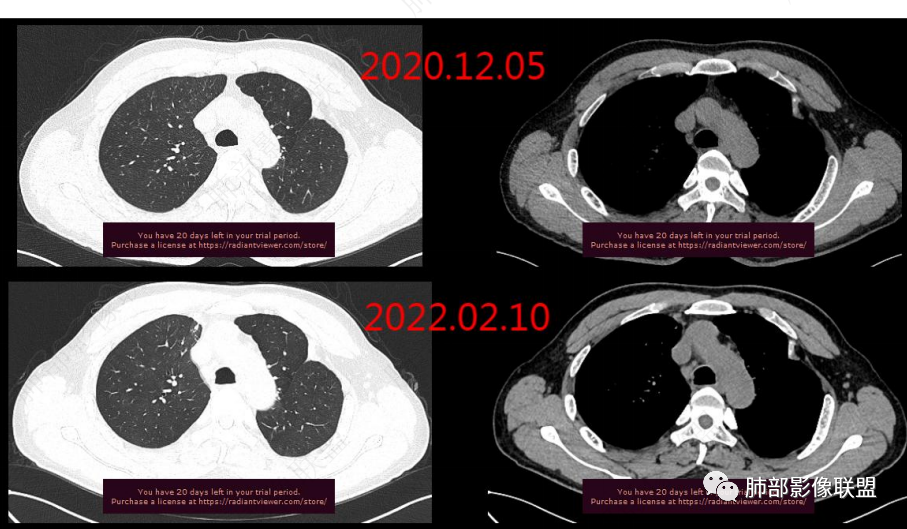

1年2个月图像变化:

右上叶前段胸膜下新发病灶;纵隔淋巴结较前增大

2020.12-2022.02右上肺新发实性病灶,边缘可见刀切征,局部边缘模糊可见絮状影及少许树芽征,邻近胸膜牵拉,增强后渐进性强化,欠均匀。考虑1.炎性病变可能大,结合左上肺胸膜处陈旧性病灶,右肺病灶考虑结核可能;2.肿块型病灶 渐进性强化,考虑炎性肌纤维母细胞瘤。3.结合肝右后叶低密度灶,增强后渐进性强化,延时期与肝脏密度相似,局灶性肝炎性改变?加IgG增高 血沉明显升高 自身免疫相关病变?建议CT下穿刺活检扫描及进一步实验室检查IG4等

2.右肺上叶纵隔旁新发实性密度病灶,密度均匀,轻度强化,未见空洞、液化坏死及钙化,血管穿行自如,支气管进入后狭窄截止。灶周磨玻璃影边界不清,病灶未见明显分叶毛刺,平直、轻度收缩、周围偶见结节影,但未见树芽征。注意纵隔胸膜侵入或突入比较明确。纵隔淋巴结轻度增大。

3.右肺容易想到的病变有慢性炎症、IGg4相关、新生物(炎性肌纤维母细胞瘤、腺癌等)。但病灶侵入纵隔胸膜应当更符合恶性肿瘤。病程进展及强化等影像特点不支持继发性肺结核。